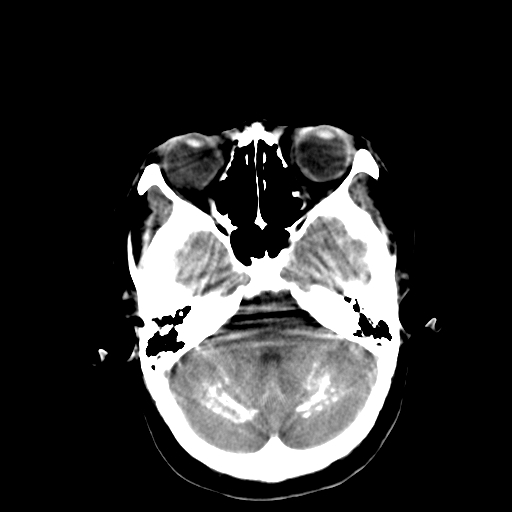

标题: CT13482:对称钙化!外伤就诊! [打印本页]

标题: CT13482:对称钙化!外伤就诊!

女,58 ,对称钙化!外伤就诊!